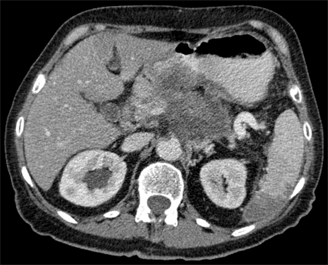

Pancreatic cancer in CT; source: Hellerhoff, Wikimedia Commons